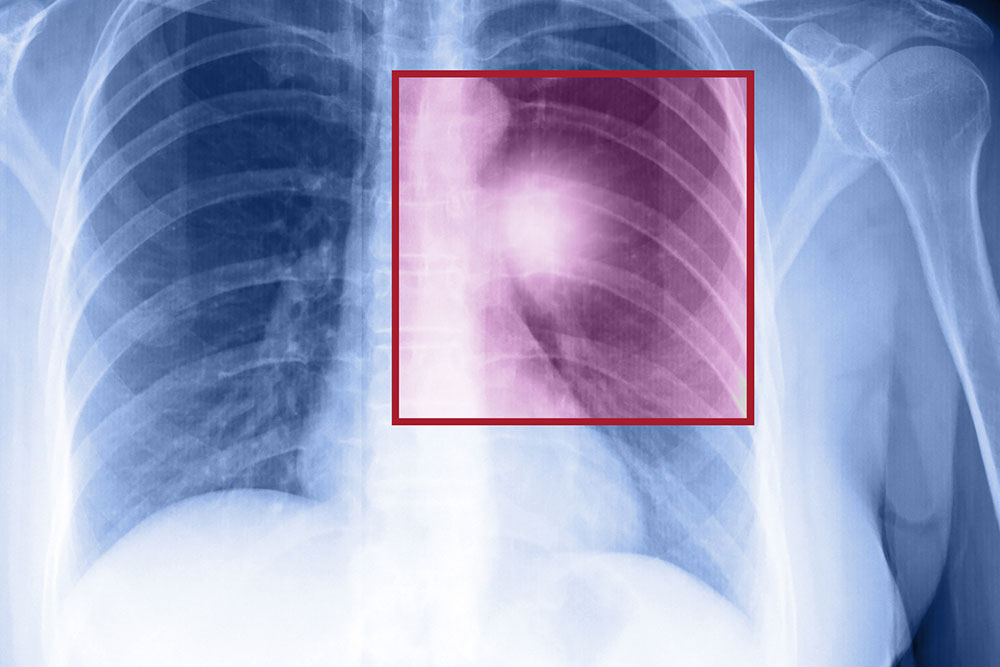

The disease is dangerous because of its ability to spread to different parts of the body. The cancer cell multiplies at the primary location and invades nearby tissues and moves through blood vessels or lymph nodes to the other parts. The most common parts where cancer is spread are the lungs, liver, and brain. Breast cancer is spread to the bone, brain, liver, or lung where it reflects the metastasis breast cancer signs.

There are no early signs of metastatic cancer. However, when they do appear, they depend on the location of the tumor. Some of the most common symptoms that are related to the lungs, liver, brain, and bones are:

- Lungs – Individuals experience a chronic cough and breathlessness.